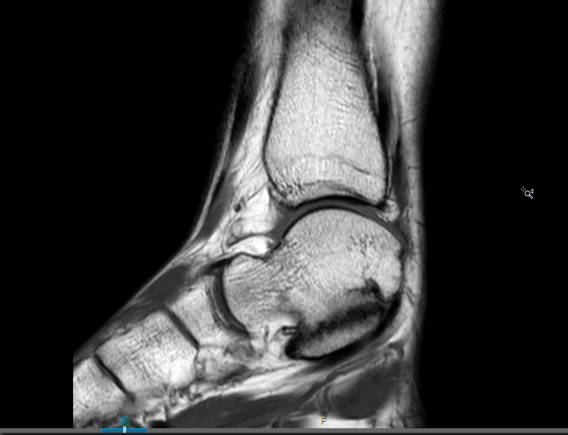

Bij klachten wordt vaak in eerste instantie gekozen voor een niet-operatieve behandeling zoals een tijdelijk gips, aanpassing van de activiteiten of aanpassingen aan de schoenen. Als dat niet helpt kan gekozen worden voor een operatie. Een coalitie kan om twee redenen klachten geven. De eerste is dat de twee botten wel een beetje aan elkaar vast zijn gegroeid maar dat er nog steeds beweging mogelijk is. Dit kan goed pijn veroorzaken, op een MRI scan zie je dan ook vaak vocht in het bot rondom de coalitie. De andere reden van pijnklachten is dat de twee botten in een verkeerde stand aan elkaar vast gegroeid zitten.

De verbening tussen het hielbeen en het sprongbeen, talocalcaneaire coalitie, is al in 1948 beschreven. Deze botten verbenen rond het twaalfde levensjaar. De klachten en de niet-operatieve (conservatieve) therapie zijn van beide coalities hetzelfde. Ook bij deze coalitie geldt dat indien het mogelijk is in eerste instantie geprobeerd zal worden de verbening die is ontstaan te verwijderen.